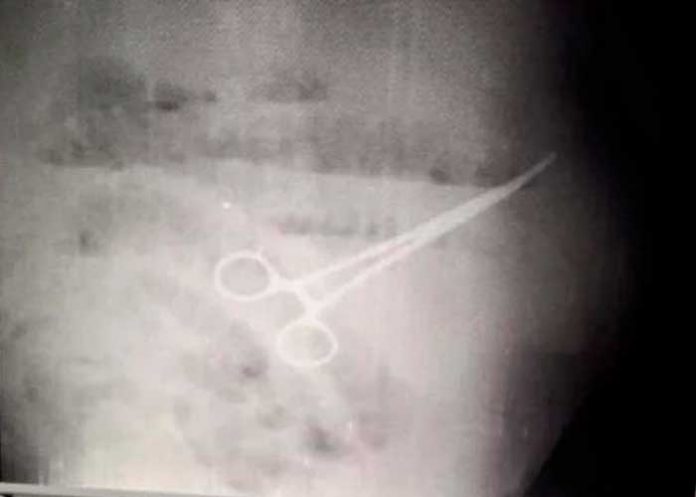

Rayos x revelaron las tijeras dentro del estómago

Los doctores no entendían lo que sucedía, así que le indicaron lavados y medicamentos que no fueron efectivos. Sin nada que respondiera sus interrogantes, le ordenaron un examen de rayos x que finalmente dejó en evidencia el error que cometieron.